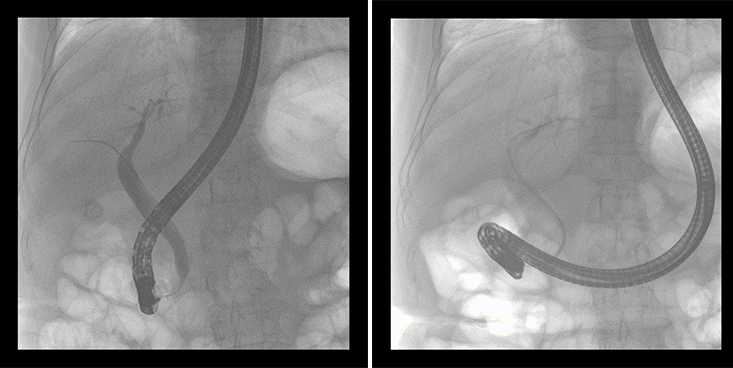

一位86歲的女性患者近來(lái)出現(xiàn)腹痛,入院后CT檢查并結(jié)合臨床表現(xiàn)被診斷為急性膽囊炎伴膽囊結(jié)石。經(jīng)專(zhuān)家團(tuán)隊(duì)協(xié)商并與患者家屬溝通,決定對(duì)患者實(shí)施經(jīng)內(nèi)窺鏡逆行胰膽管造影(ERCP)。

ERCP(經(jīng)十二指腸鏡下逆行胰膽管造影)現(xiàn)已成為比較成熟的微創(chuàng)介入技術(shù),被廣泛的應(yīng)用于臨床,ERCP也是消化內(nèi)鏡領(lǐng)域難度大、風(fēng)險(xiǎn)大、技術(shù)復(fù)雜的微創(chuàng)手術(shù),其并發(fā)癥多為致命性,ERCP手術(shù)對(duì)醫(yī)生的要求很高,因此,ERCP醫(yī)生又被稱(chēng)為“刀尖上的舞者”。因?yàn)槭中g(shù)難度較大,過(guò)程復(fù)雜,需要C形臂精準(zhǔn)的配合,對(duì)影像清晰度的要求也非常高。

普愛(ài)醫(yī)療移動(dòng)式平板中C為本次ERCP手術(shù)提供實(shí)時(shí)無(wú)損高清影像,幫助醫(yī)生精準(zhǔn)定位?!俺上裥Ч浅0簦⊥耆惠攪?guó)際大牌的醫(yī)學(xué)影像設(shè)備……”鼓樓醫(yī)院江北國(guó)際醫(yī)院內(nèi)鏡中心手術(shù)團(tuán)隊(duì)對(duì)普愛(ài)醫(yī)療移動(dòng)式平板中C的成像效果給與了高度的評(píng)價(jià)。

在消化內(nèi)科主任的領(lǐng)導(dǎo)和多科室全力配合下,南京鼓樓醫(yī)院江北國(guó)際醫(yī)院成功完成了首例ERCP手術(shù)。